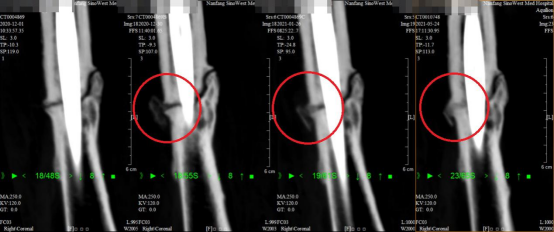

三次PRP术后断端愈合趋势明显

术后,定期复查李女士右股骨CT,动态观察断端骨痂生长情况,发现断端骨痂生长明显,断端骨密度明显提高,断端愈合趋势明显。